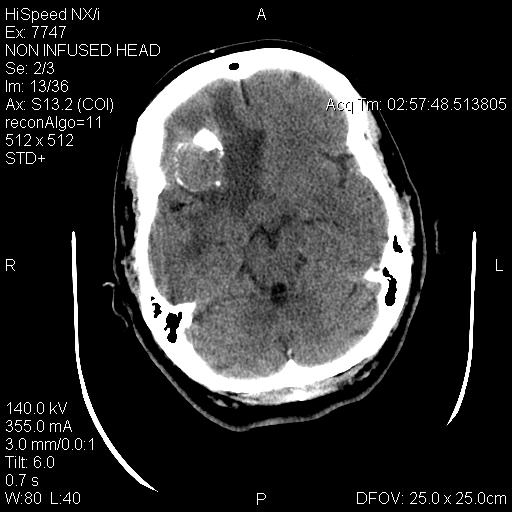

T1-weighed MR images demonstrate an extraaxial, dural based mass involving the right supraorbital region  (Panel A and B). The mass shows homogeneous enhancement  (Panel C). CT scan demonstrates as well as rim calcification (Panel E). On T2-weighed imagers, significant vasogenic edema is demonstrated despite the small size of the lesion and the extraaxial location (Panel D).